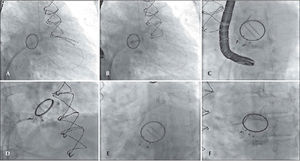

The patient developed dyspnea upon exertion, and a 2D transthoracic echocardiography was performed on November 18, 2011, which showed an ejection fraction of 60%, aortic bioprosthesis with thin leaflets without regurgitation (valve area of 1.7cm2 and maximum systolic gradients of 18mmHg, mean 10mmHg), mitral bioprosthesis with thin leaflets, preserved opening and mobility, and severe anterior paravalvular regurgitation, with maximum diastolic gradients of 13mmHg (mean 7mmHg) and slight tricuspid regurgitation. As a result of relevant symptoms and high surgical risk, a percutaneous closure of the mitral paravalvular defect was indicated and performed on November 30, 2011 (Figure 2). The procedure was performed under general anaesthesia and was initiated by puncturing the right femoral vein and the left femoral artery with 7F and 6F introducers, respectively, followed by administering a dose of 100 U/kg of unfractionated heparin. Left ventriculography was performed in the right anterior oblique projection, which showed increased end-diastolic volume and moderate inferobasal hypokinesia, as well as mild hypokinesia in the other left ventricular walls. Subsequently, a transseptal puncture was performed with a Brockenbrough needle and an 8F Mullins sheath. The paravalvular orifice was located and a 260-cm, 0.035-inch extra-stiff guidewire was introduced past it together with a 3.5, 6F Judkins right catheter curve (Johnson & Johnson Co. – Miami, FL, USA) and another similar guide with a Multipurpose 7F catheter, with the aid of 3D transesophageal echocardiography. Then, two Amplatzer™ Vascular Plug III (numbers 10–5 and 4–2) prostheses were implanted with the help of 3D transesophageal echocardiography, which was used to guide the correct positioning of the prosthesis (Figure 3). At the end of procedure, it was demonstrated that the paravalvular defect had completely disappeared (Figure 4). There were no complications during the procedure. The patient was extubated in the catheterisation laboratory and kept under observation for two hours, before discharge to the infirmary.

– In A, ventriculography in right anterior oblique view, showing mitral paravalvular regurgitation. In B, catheters in the left ventricle after moving past the mitral paravalvular orifice to start the prosthesis positioning. In C, the positioning of the prostheses and their release. In D, the final result.